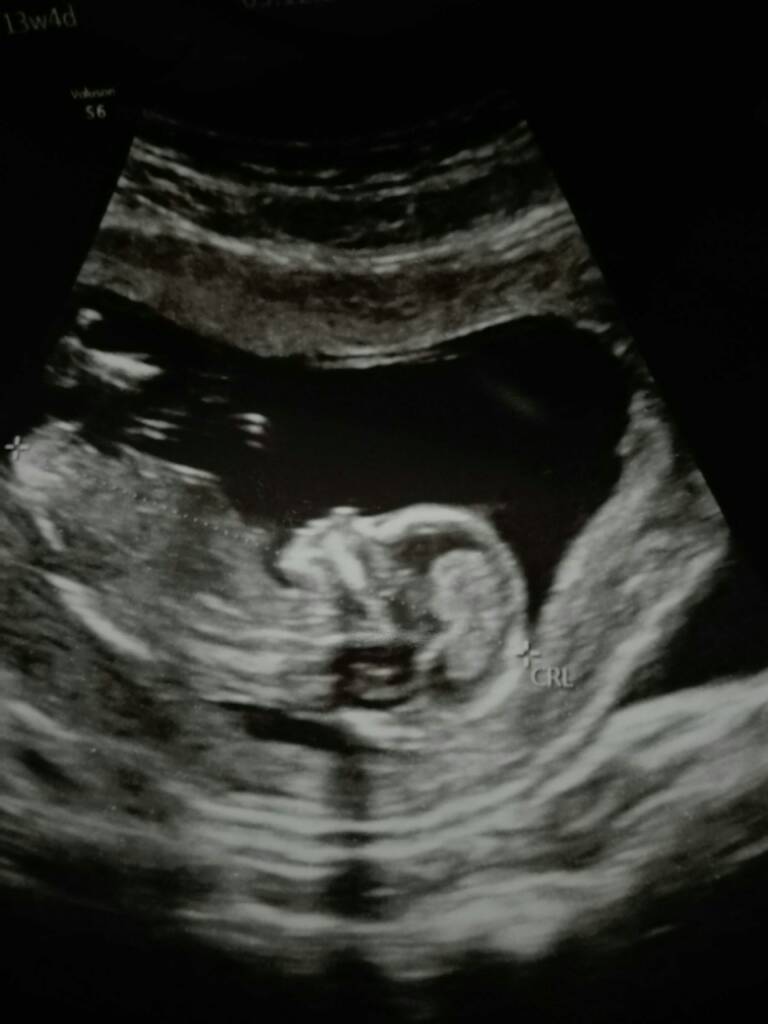

My juz po wizycie i według pani doktor czekamy na dziewczynke [emoji7][emoji7]

Maluszek juz ma 7,41 cm a dzis 13+4.

Doktor długo robila mi dzis usg bo dzidza taka ruchliwa ze co probowala ją zlapac to uciekala [emoji87] uparciuch od malego [emoji14] tak fajnie podskakiwala, otwierala buzke, machala raczkami i kopala nozkami [emoji7]